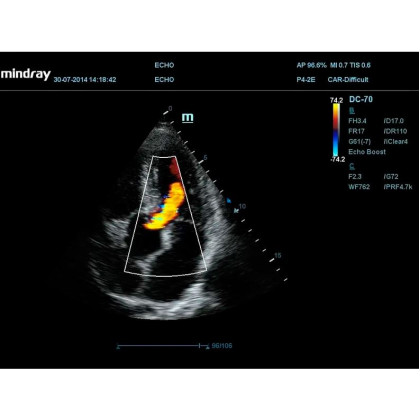

Тканевой допплер, включая цветное картирование, импульсный тканевой допплер, энергетический тканевой допплер и тканевой М-режим;

Пакет программ для исследования левого желудочка с контрастированием (доступен на датчиках SP5-1E, P4-2E).